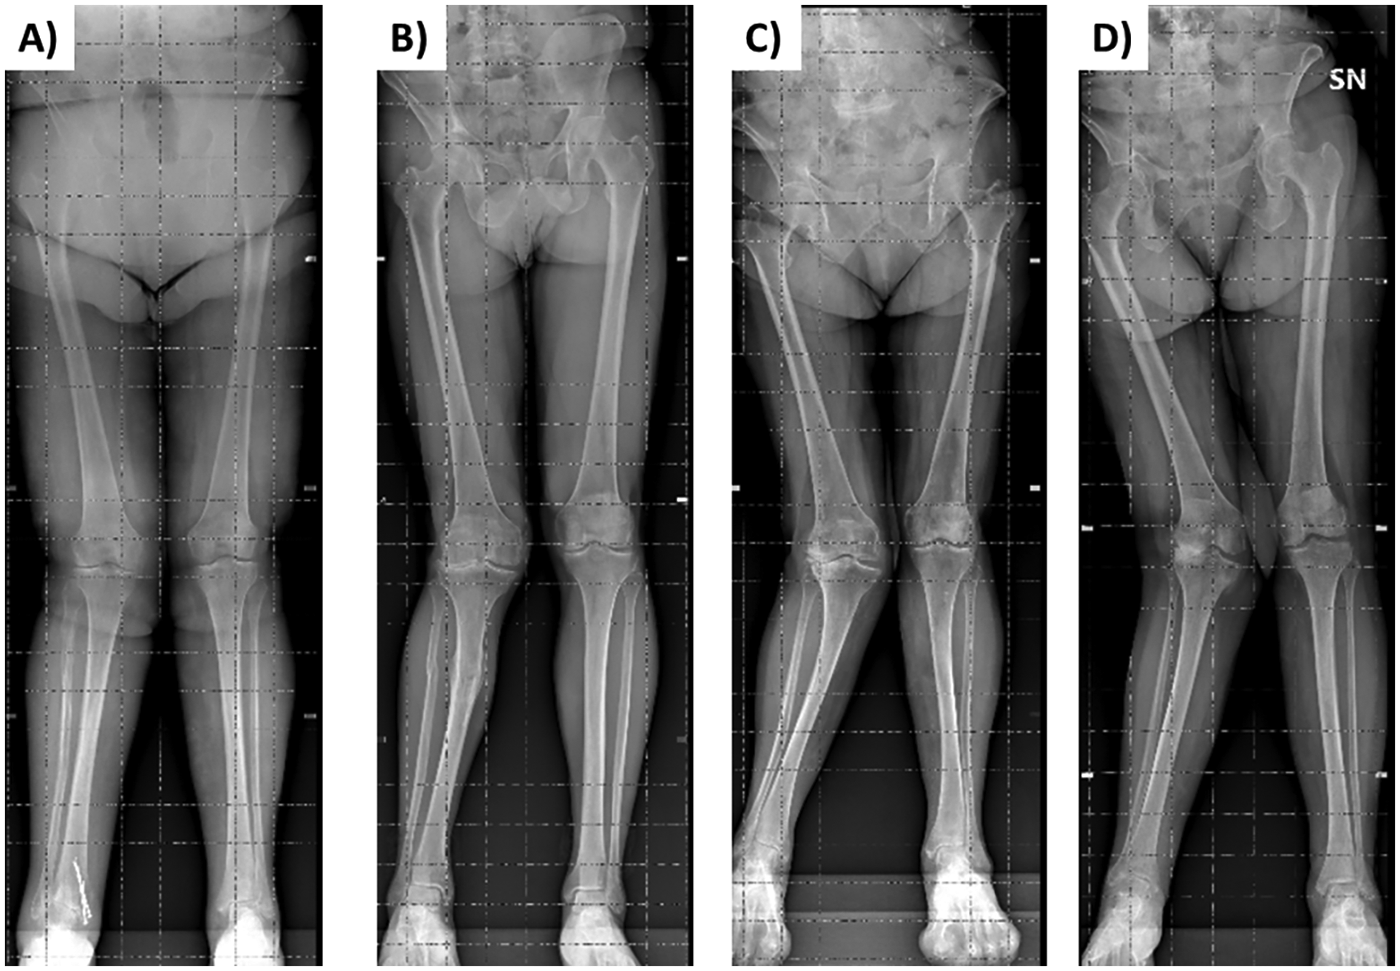

Frontal and lateral images were acquired in duplicate in all patients (scan time was around 30 s for each of the two acquisitions that were well tolerated by the patients), with the exception of 3 patients who were unable to maintain the standing position during image acquisition. Moreover, the frontal image could not be acquired in 2 patients presenting grade II valgus deformity (tibio-femoral angle between 10 ° and 20 °) and in 2 patients presenting grade III valgus deformity (angle > 20 °) (Figure 1). In addition, processing errors implied the image rejection for 2 patients: overall, body scans were not available for 9 patients (3 males and 6 females) and a total of 47 patients (19 males and 28 females) were evaluated (no statistically significant differences were observed between the two subgroups of 3 and 19 males and between the two subgroups of 6 and 28 females in age, body mass index, physical performance variables, and clinimetric variables of quality of life, comorbidities, pain intensity, pain interference: P > 0.05 for all the comparisons). Their average body shapes are shown in Figure 2 and their anthropometric and body composition characteristics are reported in Table 2. Body composition charts (38) obtained for male and female patients showed that the higher the fat mass index, the higher both the fat free mass index and the appendicular lean mass index (Figure 3): 10 out of 22 males and 21 out of 34 females had a body mass index ≥30 kg/m2, 14 out of 19 males and 24 out of 28 females had body fat >25% and >30%, and 16 out of 19 males and 21 out of 28 females had fat mass index higher than the cut-point for excess fat (>6 kg/m2 for males and >9 kg/m2 for females, respectively) (39). Moreover, 6 out of 19 males and 26 out of 28 females had waist circumference ≥102 cm and ≥88 cm (40), respectively, while 2 male patients and none of the female patients had appendicular lean mass index lower than the cut-point for low mass (<7.26 Kg/m2 for males and <5.45 Kg/m2 for females) (41).

Figure 1

Weight-bearing anteroposterior radiographs of the entire lower extremities of 2 patients presenting grade II valgus deformity [tibiofemoral alignment for the right side of 11 ° in panel (A) and 13 ° in panel (B)] and of 2 patients presenting grade III valgus deformity [alignment for the right side of 22 ° in panel (C) and 25 ° in panel (D)].

The pre-operative assessment of comorbidities (e.g., obesity, frailty) and other factors (e.g., type of surgery, physical performance) is widely used in the clinical practice to predict the peri-operative risks. For example, in case of body mass index (BMI) in the range 30–40 kg/m2, a patient is classified as having a mild systemic disease (according to the ASA Physical Status Classification System) (42) that may contribute to increase the peri-operative risk. Although BMI is a globally applied phenotypic descriptor of adiposity at the population level, its limitations for assessing weight and predicting excess body fat at the individual level are well known (43–46). Consistently, previous (38) and our body composition charts showed that a given BMI embraces a wide range of percentage fat. Thus, previous and present data suggest that moving beyond BMI is required to precisely characterize the health status of individual patients. This is the first study, to our knowledge, showing in a real-world setting the feasibility of a digital anthropometric approach to quantify and characterize the increased adiposity in patients with late-stage knee osteoarthritis. The observation that excess adiposity was associated with an increased abdominal circumference (i.e., a marker of visceral adiposity) in both male and female patients is in agreement with recent studies showing that body shape changes (i.e., increased “apple-shaped” phenotype due to a body weight “shift” from the lower to the upper body, especially to the waist) occurred over the last decades in both men and women of American (47) and European (10) populations. Thus far, smartphone camera technology has only been used to estimate percent body fat and only in academic research settings. To our knowledge, this study is the first investigating in a real-world setting (and through an innovative digital approach) the appendicular lean mass (i.e., a proxy of muscle mass) that was normal in female patients and reduced in some male patients. On the basis of our findings, we suggest that the pre-operative prognostic assessments of patients with late-stage knee osteoarthritis could be improved in the clinical practice through the acquisition of “e-tape” measurements of body size and composition (such as waist circumference, fat mass index, and appendicular lean mass index) that can be more informative and acceptable compared to standard anthropometric measurements (based on weight and height assessment or on the identification of anatomical landmarks through observation and palpation). However, the Mobile Fit app adopted in the present study failed to capture the frontal image in some patients presenting grade II or III valgus deformity: therefore, the avatars of these patients were not available. Methodological implications of this observation are twofold. First, the algorithms adopted to extract the frontal silhouette (that is required in combination with the lateral silhouette to generate the three-dimensional avatar) need to be improved for the use of this app in patients with anatomical limb deformities. Second, three-dimensional scanners could be required to evaluate patients presenting with varus or valgus deformities. It may be hypothesized that the technology of three-dimensional scanners is less sensitive to limb deformities compared to mobile digital anthropometry applications (using photographic images of static subjects, either from anterior and lateral or anterior and posterior views).